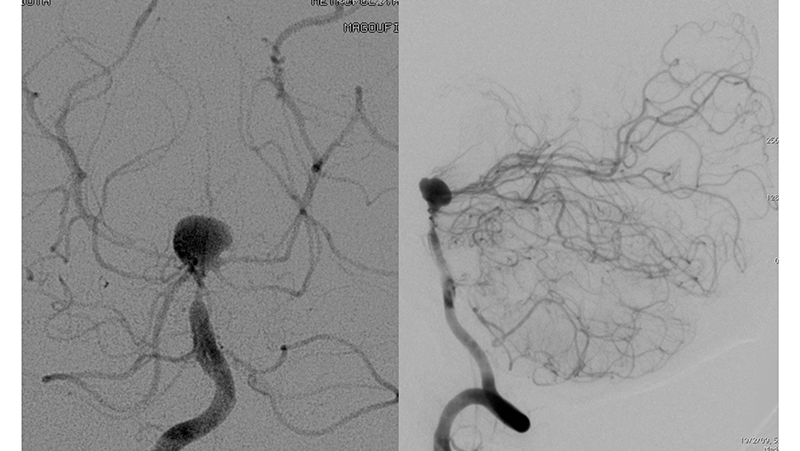

Εικόνα 1 και 2: Ραγέν ανεύρυσμα της κορυφής της βασικής αρτηρίας, το οποίο έχει ευρύτατο αυχένα. Η ασθενής ευρίσκεται ήδη σε φάση προχωρημένου αγγειοσπάσμου. Το ανώτερο τριτημόριο της βασικής αρτηρίας παρουσιάζει σημαντικό σπασμό με ελάττωση της διαμέτρου του.

Ταυτόχρονα τριχοειδική απεικόνιση του Ρ1 και Ρ2 τμήματος των οπισθίων εγκεφαλικών αρτηριών αμφοτερόπλευρα, λόγω έντονου αγγειοσπάσμου.